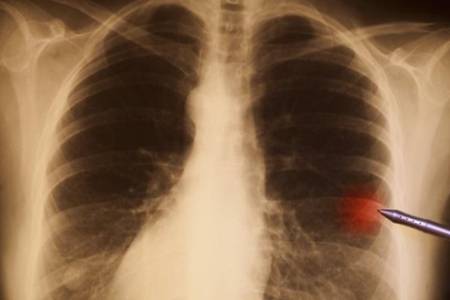

很多人在体验的时候会发现肺部有小结节的情况,肺结节到底是怎么回事?体检发现肺结节该怎么办?其实,肺结节是指肺实质内直径≤3 cm 的类圆形或不规则病灶,影像学表现为密度增高的阴影,多数情况下不用治。接下来,大家就和小编一起来看看吧。

不过,肺部小结节不一定就是肺癌,虽然肺癌确实是会引起肺部小结节,但它并不是引起肺部小结节唯一原因,其他因素(真菌感染、错构瘤、炎性假瘤)等良性病变疾病也都会导致肺部小结节的出现,所以不能将肺部小结节跟肺癌划上等号。